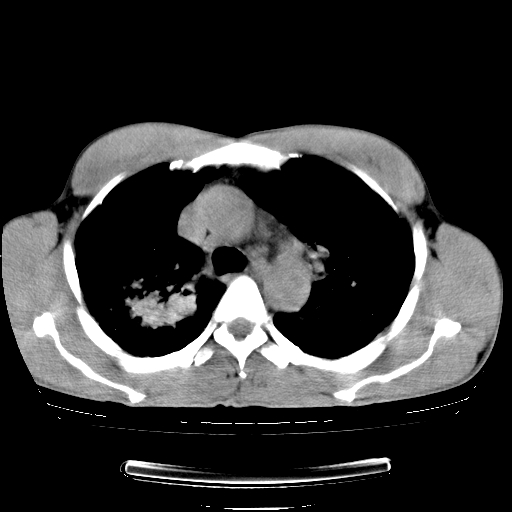

以下是引用yangyudong333在2008-4-29 5:38:00的发言:[br]比较典型的矽肺结节.支持[br]诊断依据:[br] 1.x线表现:[br] ①典型矽肺为多发直径 1~3mm 小结节,即矽结节,由胶原纤维和硅尘构成,可融合成团块,好发于上肺。[br] ②团块周围常有肺大泡。[br] ③胸内淋巴结增大、钙化。如肺门淋巴结呈蛋壳样钙化有助于与其他尘肺区别。[br] ④胸膜常广泛粘连、增厚。[br] 2.ct表现[br] ①两肺散在大小较为一致的小结节影,其密度较高,边界清楚。[br] ②小结节可融合为较大团块影,直径约 1cm ,甚至可达 10cm以上,易发生在上叶。[br] ③小结节周围常并有小叶中心气肿或弥漫性肺气肿。

以下是引用liuyue在2008-4-28 22:30:00的发言:[br]比较典型的矽肺结节.[br]请结合临床及化验除外矽肺合并肺结核之可能.